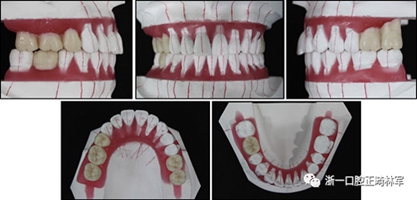

一名因多顆牙齒缺失和牙周損傷的49歲婦女被牙周科送往國民健康保險服務(wù)一山醫(yī)院的正畸科進行跨學(xué)科綜合治療。多顆后牙已在10天前被拔除。她的主訴是前牙列擁擠,她想改善美觀和功能。她的病史沒有提供有用信息,她沒有顳下頜關(guān)節(jié)紊亂的跡象。口外檢查顯示面部對稱,休息位時嘴唇不適,尖銳鼻唇溝和突出的嘴唇。她的下頜牙齒中線偏移到面部中線的左側(cè)(圖1)。

圖1. 治療前面部和口內(nèi)照片

口腔內(nèi)由于牙周炎,她的上頜右側(cè)第一和第二前磨牙,上頜右側(cè)第一和第二磨牙,上頜左側(cè)第一和第二磨牙以及下頜右側(cè)第一磨牙缺失。牙周探查顯示在磨牙區(qū)域和下頜骨左側(cè)側(cè)切牙區(qū)有深的牙周袋,還存在出血(表I)。上頜骨和下頜骨前牙擁擠,左側(cè)側(cè)切牙存在反合,下頜左側(cè)側(cè)切牙發(fā)過度萌出。覆蓋是5毫米,上頜切牙是唇傾的。在上頜弓中,尖牙和前磨牙是近中傾斜,右側(cè)尖牙過度萌出。而且,下頜右側(cè)第二磨牙向近中傾斜。尖牙處于I類關(guān)系,但無法評估磨牙關(guān)系(圖1和2)。

圖2. 治療前牙齒石膏模型